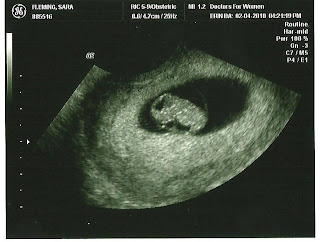

Based on how I am measuring, they have moved my due date to September 14th! Originally, it was September 18th. I put a little ticker on the bottom of my blog here so you can watch and see how baby is growing. :)

Right now, I am almost 9 weeks! And Baby Lovie has grown to the size of a small grape!

Baby lovie is starting to look more human, and less reptilian, haha. The tail (which you can see in the ultrasound) is gone at 9 weeks. Baby's heart finishes dividing into four chambers, and the valves start to form — as do the tiny teeth. Also, baby's organs, muscles, and nerves are kicking into gear. The external sex organs are there but won't be distinguishable as male or female for another few weeks. Baby's eyes are fully formed, but the eyelids are fused shut and won't open until 27 weeks.

Finally, baby is getting ready to put on some serious weight. Which means Mommy is too!

Please keep praying that everything goes smoothly. By the next ultrasound, in 2 weeks, there should be a lot more detail in the ultrasound picture, as well as pictures of my pregnancy bump (I’ve just started to pop). :)